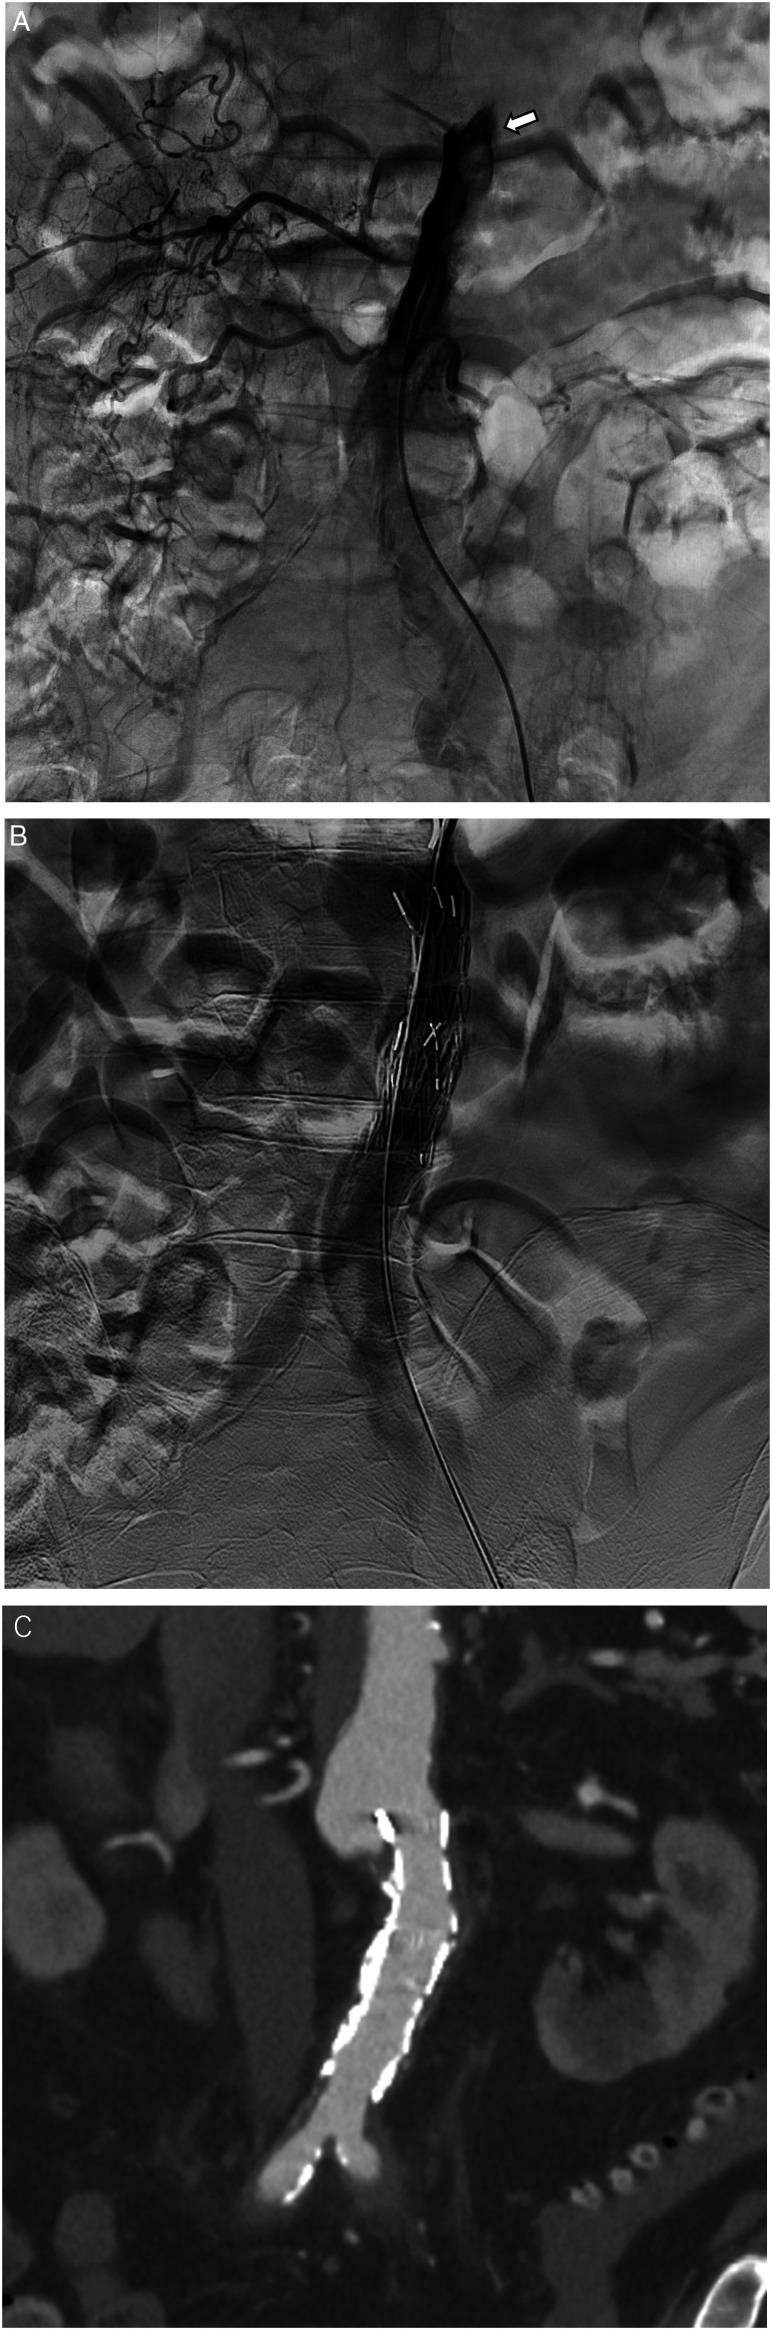

我们报告一例复杂的孤立性肾下腹主动脉夹层(IAAD)用支架移植治疗。一名79岁男性,表现为急性双侧下肢疼痛。2小时后行CT增强检查,发现IAAD所致严重的腹下主动脉狭窄。血管造影发现在IAAD上端下方有原发性撕裂。在远端放置一个较小的支架以避免支架诱导的新进入,在近端放置一个较大的支架以覆盖原进入。手术后狭窄立即改善,疼痛得到缓解。对于IAAD来说,放置支架关闭入口似乎是一种有效的方法。

We report a case of complicated isolated infrarenal abdominal aortic dissection (IAAD) that was treated with stent graft. A 79-year-old man presented with acute bilateral lower limb pain. A contrast-enhanced CT performed 2 h later revealed sever stenosis of infrarenal abdominal aorta due to IAAD. Angiography identified a primary tear just below the upper end of the IAAD. A smaller stent graft was placed distally to avoid stent graft-induced new entry, and a large stent graft was placed proximally to cover the primary entry. The stenosis improved immediately after the procedure, and pain relief was achieved. Stent graft placement for entry closure appeared to be an effective for IAAD.